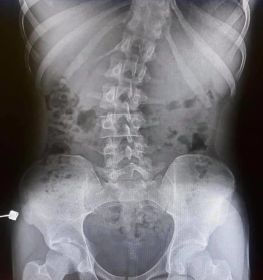

Doğuştan gelen skolyoz hastalığı, doğumdan itibaren omurga kemiğinin yapısının bozuk olması durumudur. Tedavisi en zor olan türdür.

Omurga eğriliği yaşan insanlarda eğer eğrilik 40 dereceyi aşmış ise cerrahi operasyon ile tadavi edilir. Bu şekilde bir tedavi çok riskli ve zordur. Ardından ise mutlaka fizik tedavi ek olarak da korse tedavisi uygulanmalıdır.

Skolyoz hastalığı omurgaların dizilimindeki düzensizlik ve yamukluktur. Çoğunlukla çocuklukta görülen hastalık yetişkinlerde de az da olsa görülebilir. Sağa sola omurgalardaki çıkıntıların zamanla omurilik eğriliği bir hale getirdiği hastalıkta erken tanı çok önemlidir. İster yetişkin isterse çocuk olsun erken teşhis sonucunda fizik tedavi yöntemi işe yarar. Hastalık özellikle kişilerin günlük yaşantılarını etkileyen olumsuzluklar yaşatan ve yaşam kalitesini düşüren bir rahatsızlıktır. Geç kalınmadan tedaviye başlanmalıdır.